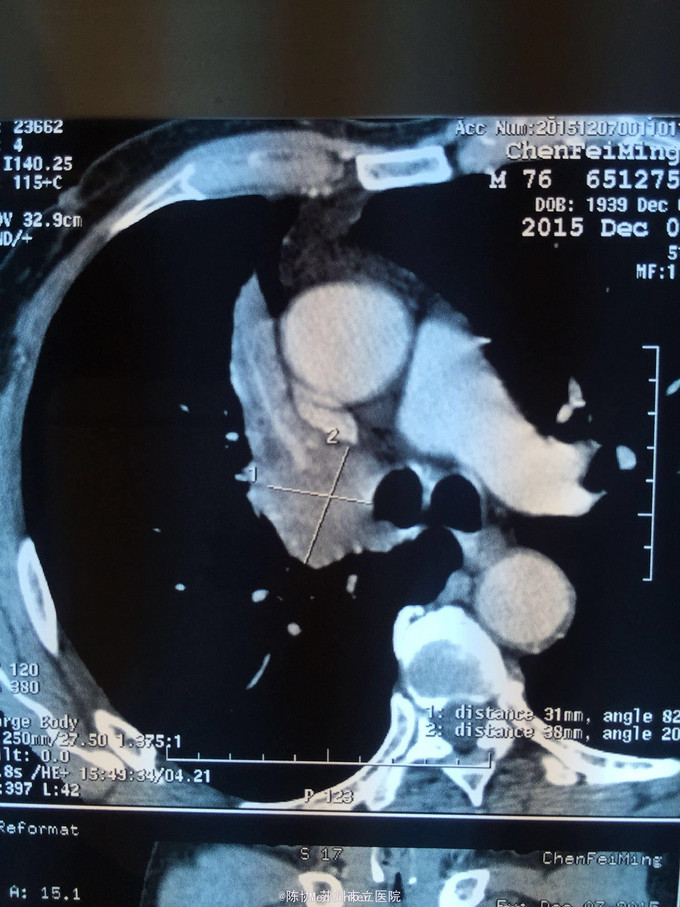

主诉:体检发现右上肺不张半月 77岁男,半月前体检发现右上肺不张,无不适。无消瘦,无咳血,无干咳。去年4月右上肺炎,抗生素治愈,当时CT未见肺肿块。入院支气管镜发现右上支气管开口组织增厚闭塞,开口近侧有隆起约3x3平方毫米,取活检5块病理示中度非典型增生。CT提示在右侧主支气管外侧有30x30平方毫米块影,压迫右上支气管开口处。三大常规和生化检查正常,肿瘤指标正常,TAP正常。

右侧中央型肺癌 重做支气管镜,精于定位找到病症组织,获得病理诊断来指导治疗。 胸外科医生不建议手术,理由是肿瘤位置靠近主支气管和气管,袖状切除不一定看干净。 请问正确的诊断,和比较合理的治疗方法是什么?求助大家思考评论